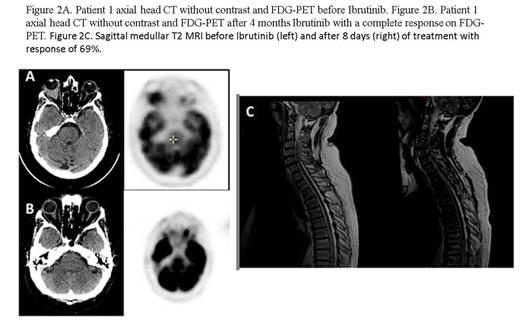

Results. All patients were alive, respectively at 4 and 3 months and two weeks. CNS response of patient 1 by CT showed a tumor reduction of 81% with a complete CNS response on TEP at 4 months (Fig 2A and 2B). A complete response of peripheral nodal involvement was also observed. Patient 2 was evaluated with CSF study and CNS MRI. We observed an important decrease of CSF involvement (from 900 cells/mL to 100 cells/mL) as early as day 15 (Fig 1), and a response of the retro-orbital lesion (-23%). However an increase of lymphoma cells in CSF was observed at day 64 and was associated with 88 % decrease in Ibrutinib plasma exposure. At the same time, Ibrutinib CSF concentration measured at Tmax remained stable from day 8 to day 36, ranging from 1 to 3 ng/mL, with a CSF concentration/plasmatic concentration ratio of 0,019. Patient 3 rapidly improve his clinical exam with a recuperation of motor deficit and sensitive level at day 8. MRI was evaluated at day 8 of Ibrutinib and showed a spectacular response with a 69% decrease of myelitis trasverse and a regression of contrast enhancement (Fig 2C).